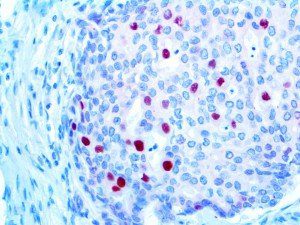

It is the ICU physician who is most likely to witness one of the deadliest manifestations of the abnormal immunological response, the cytokine storm syndrome (CSS). This response is also referred to by some as the cytokine release syndrome (CRS). CSS is characterized by continuous activation and expansion of macrophage and lymphocyte populations, which secrete large amounts of cytokines, causing the cytokine storm. This massive cytokine release is akin to hemophagocytic lymphohistiocytosis (HLH) disease, a syndrome characterized by initial unchecked and persistent activation of cytotoxic T lymphocytes and NK cells.

Clinical and laboratory manifestations of HLH include fever, enlarged liver and/or spleen, neurologic dysfunction, coagulopathy, liver dysfunction, cytopenias (i.e., low levels of erythrocytes, leukocytes, and/or platelets), hypertriglyceridemia, hyperferritinemia, hemophagocytosis, and eventually diminished NK cell activity as the immune system becomes progressively paralyzed. HLH can be familial (primary HLH) or secondary to another disease process (sHLH), such as rheumatic disease, in which it is referred to as macrophage activation syndrome (MAS, characterized by elevated ferritin).